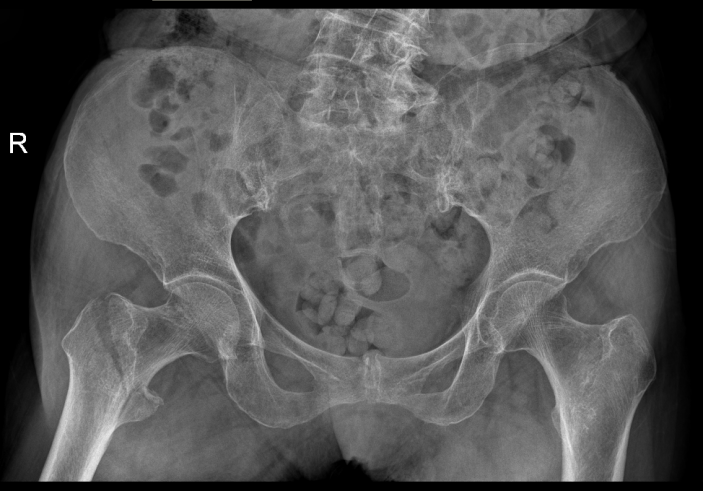

△骨科于15日、16日收治的另外兩位高齡患者

△術前

△術後